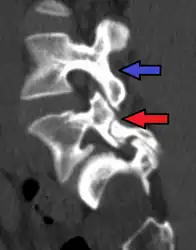

Anterolisthesis L5/S1. Blue arrow normal pars interarticularis. Red arrow is a break in pars interarticularis